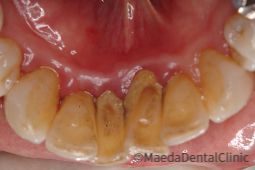

喫煙の歯周病への影響

喫煙は歯周病の主要なリスクファクターです。喫煙者は歯周病の進行が速くなり、歯周病治療の結果が思わしくないことが多いです。本格的な歯周病治療を行う際は必ず禁煙しましょう。

喫煙によって歯肉が弱くなる

喫煙するとタバコに含まれるニコチンが血管を細くしてしまい、歯肉の血液の流れが悪くなります。歯周病菌が侵入してきたときに戦ってくれる白血球などがうまく行き渡らないので、菌の侵入を許してしまいます。また、歯周病の特徴として歯磨きのときの歯肉からの出血がありますが、喫煙で血管が弱った歯肉の場合、出血せずに病気の発症・進行に気づかない事があります。